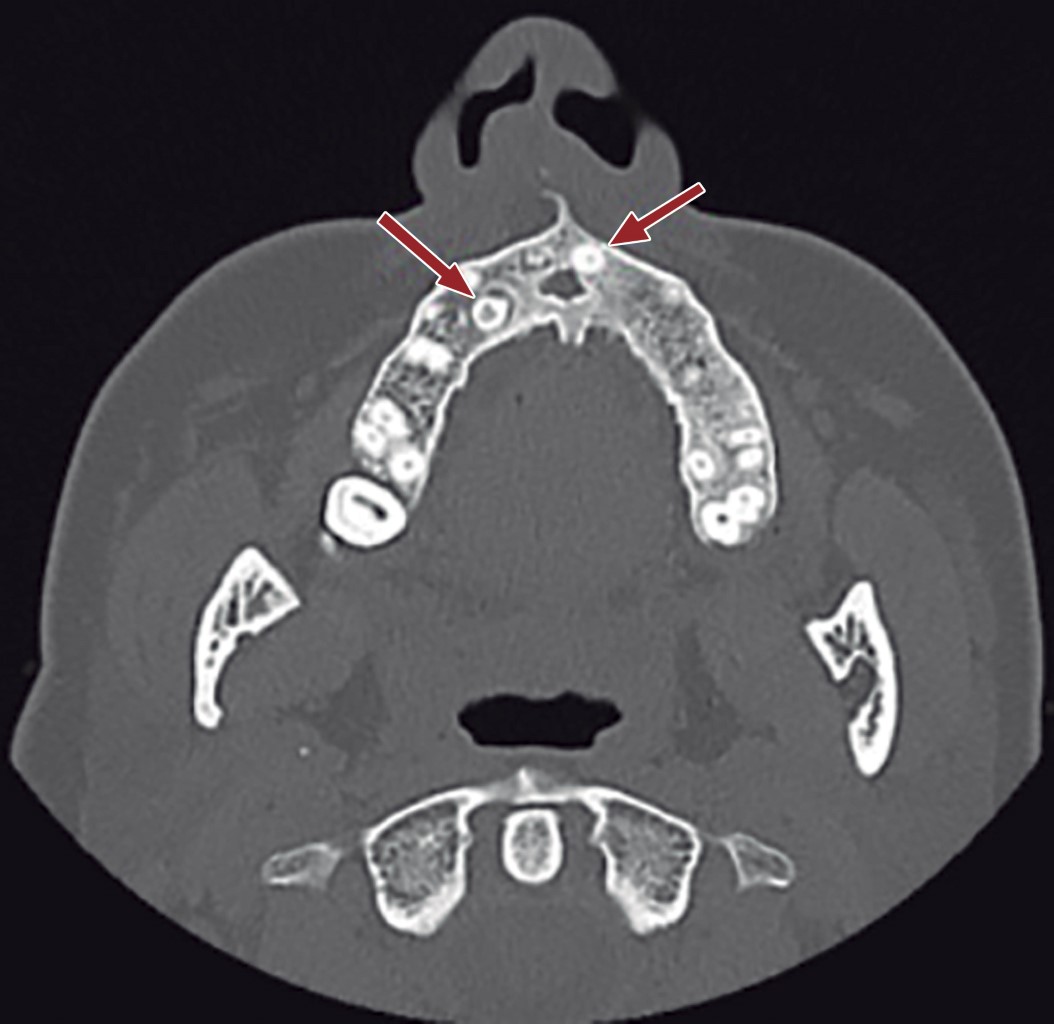

Al examen físico segmentario presenta septodesviación obstructiva/oclusiva anterior hacia fosa nasal derecha, con sospecha de secuelas de fractura de tabique anterior cartilaginoso, desviación de columela nasal hacia la derecha, laterorrinia a la derecha positiva e hipertrofia de cornetes. Es derivada a nuestro servicio maxilofacial por equipo de otorrinolaringología por hallazgo en tomografía computarizada previo a cirugía nasal funcional de dos dientes supernumerarios maxilares (Figura 1) y canal del nervio nasopalatino con un calibre considerablemente mayor a la norma (Figura 2). Uno de los dientes supernumerario es un mesiodens que se encuentra rotado, invertido con la cúspide hacia cefálico en el tabique nasal anterior y el otro en posición palatina en relación al canino superior izquierdo. Al examen clínico no se palpa mesiodens por cavidad oral ni cavidad nasal.

Figura 1